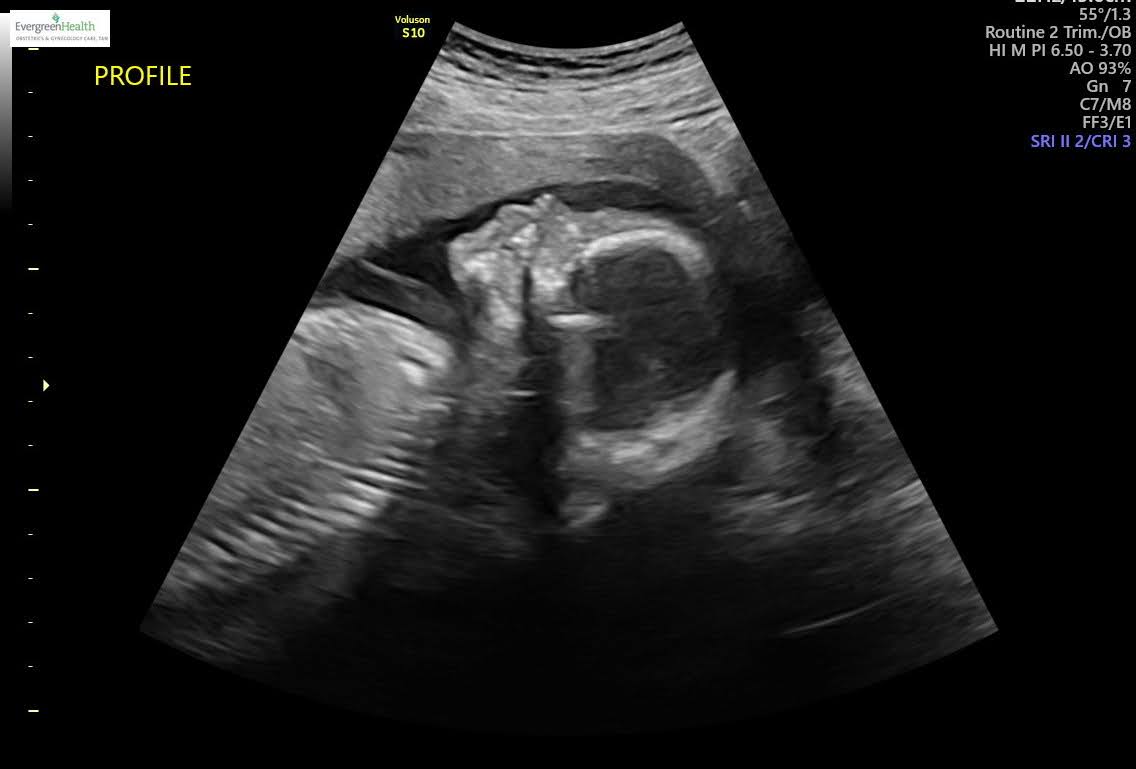

I'm not usually a big braggart but I just got back from another ultrasound and... my son has bones!

Look at this boney little man.

This one is cute because he has his little hand on the side of his head like babies do, and I also think his little mouth is moving. Could have the hiccups or just practicing swallowing.